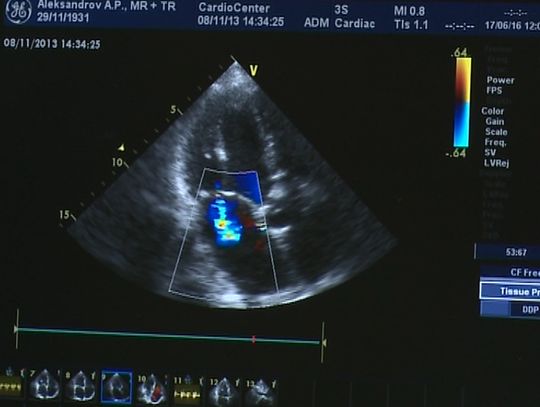

Врачи отмечают улучшение условий оказания помощи в кардиоцентре - проведен ремонт, закуплено новейшее оборудование, внедрены новые методики.

Михаил Рязанов, заведующий четвертым кардиохирургическим отделением: «Мне бы хотелось сказать словами одной из сотрудниц: стало лучше, чем дома. Полный ремонт, мебель, коечный фонд, прикроватные мониторы. Полное переоснащение...»